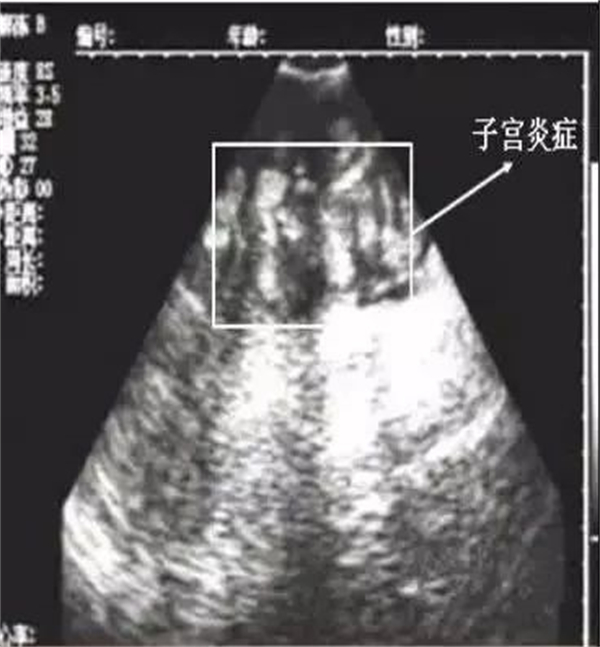

很多人把产后3-4天外阴是否有恶露排出做为子宫炎症是否消除的依据。事实上,在产后3-4天后,即使产后未能正确护宫,子宫内恶露也会由于子宫颈口关闭而被堵塞,呈现外阴干净的情况,让大家误以为子宫炎症已经消除。当出现上述案例的情况时,用B 超进行子宫检查我们会发现这种如下图情况。这是产后7天以后, B超检测的子宫图片,从B超图片上可以看到,子宫内炎症并没有完全消除。